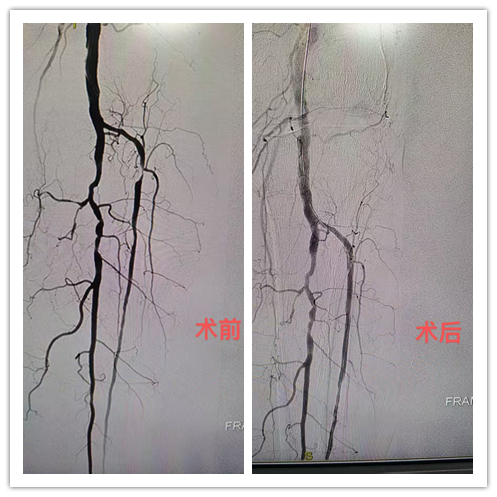

微创介入一针疏通血管,七旬老人告别"腿梗"之苦

入院体查发现,史奶奶的左足背动脉完全摸不到搏动,脚部温度明显偏低,若不及时治疗,可能导致肢体坏死。经仔细讨论后,介入血管外科三病区手术团队在局麻下为患者实施了左下肢动脉腔内成形术。术中,通过超声引导,从大腿穿刺插入细导管,用球囊扩张狭窄的血管,并植入支架保持血流畅通。手术伤口仅针眼大小,术后患者的左腿疼痛明显减弱,皮肤温度回升。“手术后的当天晚上我就睡了个整觉!史奶奶欣喜地告诉医生。